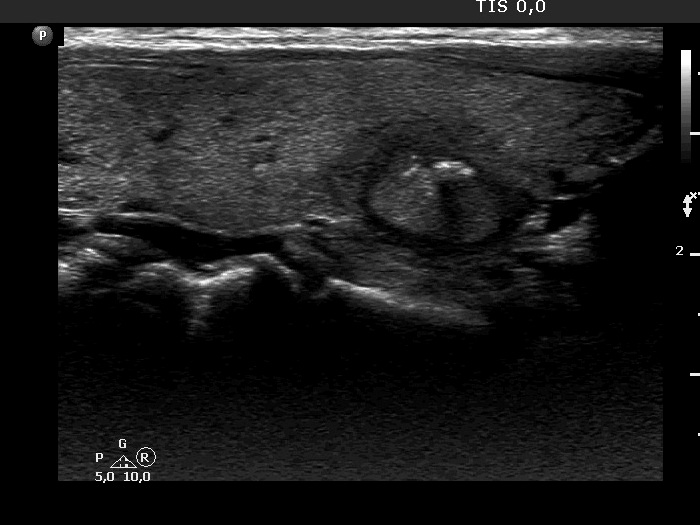

Right lobe, longitudinal scan

Right lobe, another longitudinal view. The nodule has hyperechoic figures.